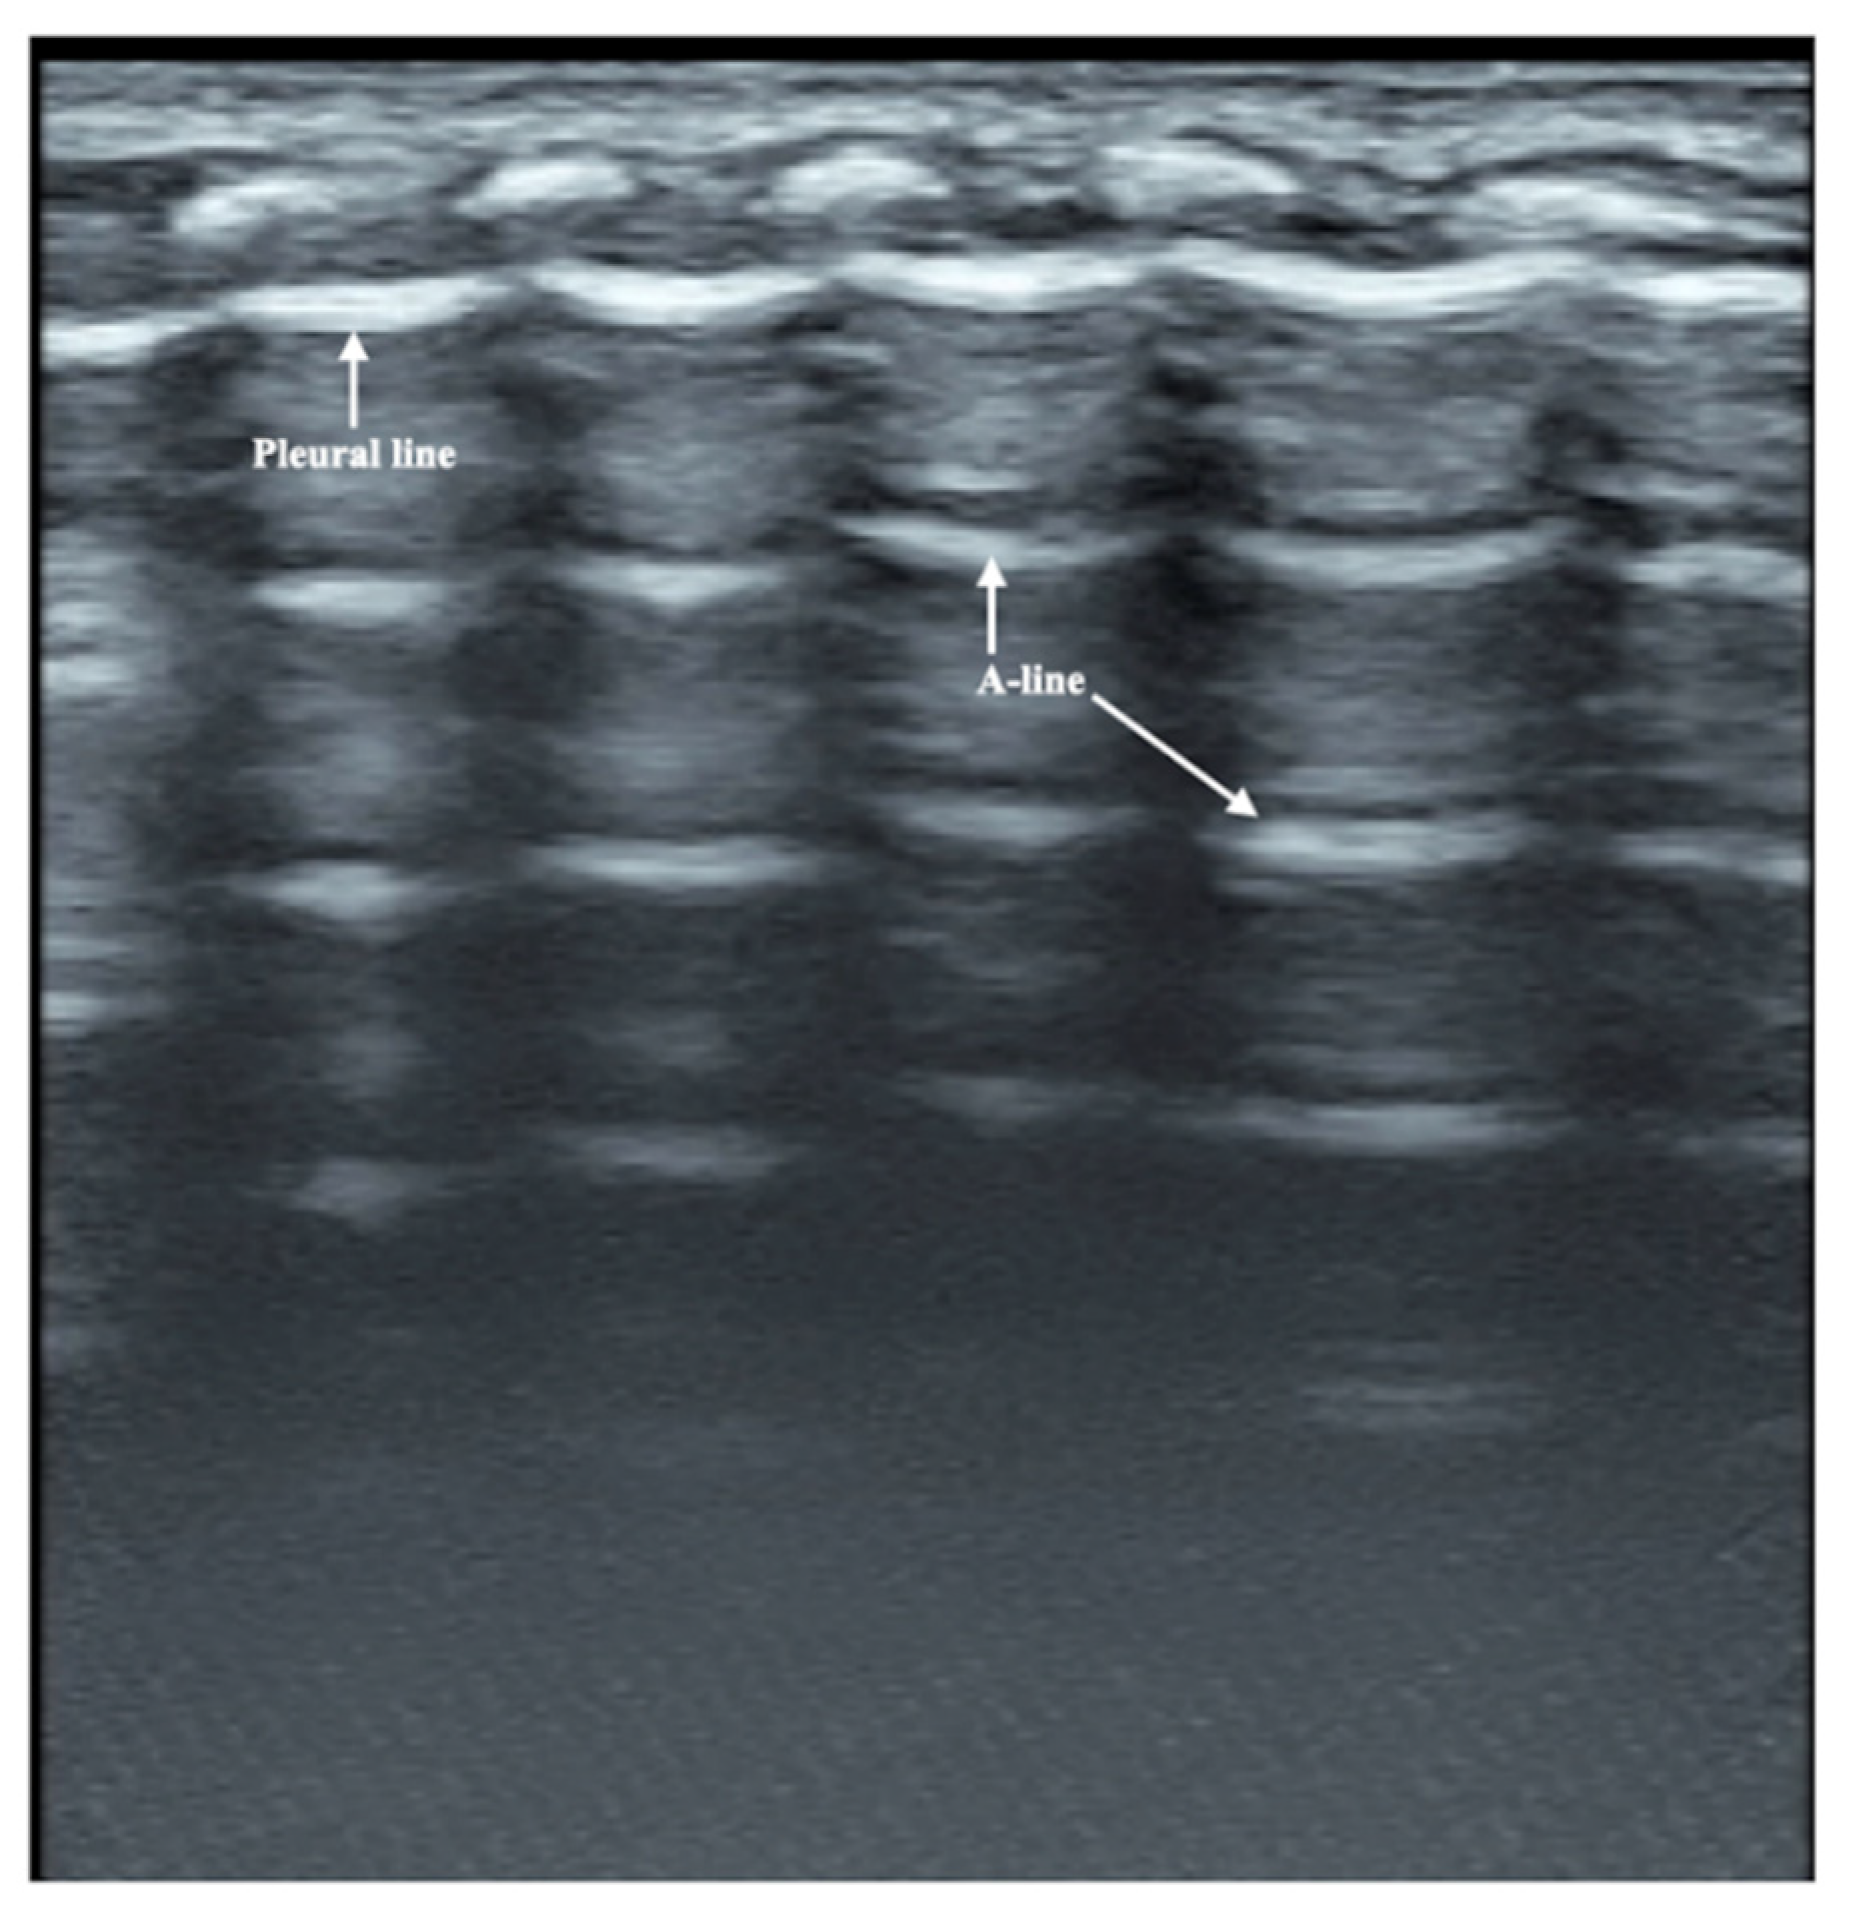

Figure 3.

Normal lung ultrasound manifestations. On B-mode ultrasound, the pleural line and A-line show smooth, regular and hyperechoic lines arranged in parallel and equidistant from each other. Together, they form a kind of bamboo-like performance, which is known as the bamboo sign.

The patient was a male premature infant delivered by cesarean section because of placental abruption at gestational age 28 weeks with a birth weight of 900 g. The infant was hospitalized at the NICU due to severe respiratory distress and subsequently complicated with diffuse intravascular coagulation (DIC) at the late stage of hyperfibrinolysis. A blood examination showed a white blood cell count (WBC) of 29.3 × 109/L and a c-reactive protein (CRP) of >150 mg/L (normally, <2.0 mg/L) at 4 h after birth. The patient’s condition stabilized after 10 days of invasive mechanical ventilation, anti-DIC and broad-spectrum antibiotic treatment. However, from the 14th day after birth, the infant had persistent fever (a temperature higher than 38 °C), and dyspnea reoccurred. The fever lasted for more than two weeks with a temperature >38 °C (highest 38.8 °C); the WBC count was elevated between a total of (21~29) × 109/L with a significantly elevated neutrophil ratio (>80%); the CRP increased (>150 mg/L for more than 2 weeks) for more than three weeks; the platelet count continued to decrease for more than 2 weeks (minimum <10 × 109/L); and three blood cultures and three deep sputum cultures and peripherally inserted central catheter (PICC) tip cultures showed no pathogenic bacterial growth. An LUS examination showed a large area of lung consolidation forming significant atelectasis in both lungs. The left lung mainly involved the upper lung field, while the right lung was almost consolidated in all lung fields (Figure 1). There was almost no bronchial inflation in the consolidation area, but a Doppler ultrasound showed that blood supply was still present well in the consolidated lung fields (Figure 2). This is very different from the normal lung images, which present as a bamboo sign on a B-mode ultrasound (Figure 3). During this period, the infant successively received meropenem, imipenem, linezolid, the fourth generation of cephalosporin, metronidazole and other antibiotics, and his condition still did not improve. Although both mycoplasma and chlamydia antibody/antigen tests were negative, when the antibiotics were adjusted to macrolide antibiotics (azithromycin) on day 28 postnatally, the temperature of the infant fell below 38 °C that day, and then, the temperature remained normal. Then, with the informed consent of the parents, blood samples were collected for metagenomic next-generation sequencing (mNGS) testing for pathogens, and the detection result confirmed legionella pneumophila infection. Therefore, the patient continued to receive azithromycin. The temperature remained normal, and the WBC, platelet and CRP levels gradually returned to the normal range within a week. The LUS showed that the scope of the lung consolidation gradually narrowed until it disappeared completely after 20 days (Figure 4). The total treatment period lasted for nearly 4 weeks, and the patient was discharged on the 70th day after birth, with a weight of 2620 g at that time. The infant was followed up for nearly 12 months and experienced normal growth. Over the past decade, LUS has been widely used in the diagnosis and differential diagnosis of neonatal lung diseases [3,4], including neonatal pneumonia [5,6,7]. LUS has a number of advantages over CXR; it should serve as a complementary diagnostic method in providing accurate, timely and reliable information [8,9]. The major finding of the LUS examination in this patient was the large-area consolidation in the bilateral lungs. There were a few air bronchograms in the consolidation area of the left lung but no air in the consolidated area of his whole right lung, which meant serious atelectasis (Figure 1). However, Doppler ultrasonography showed that there was still good blood supply in the lung tissues with consolidation and atelectasis (Figure 2). The presence of blood supply is a prerequisite for the consolidation and atelectasis of lung tissue to recover to normal [2].